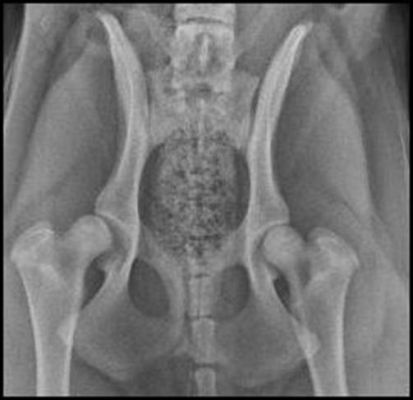

These are the hip radiographs of my 7.5 month old female GSD. She had a forelimb lameness but was sound in the rear. We xrayed elbows and hips while under sedation. The orthopedic surgeon suggested elbow arthroscopy and a TPO of her right hip to prevent future osteoarthritis as it is obviously subluxated. Of course if I can get away without doing surgery that would be preferable. Any comments appreciated.

Would have been nice to see the elbows as well. With the hip I would wait untill it actual makes problems. Just remember that the x-rays are done in a very unatural position. The socket appears to have enough depth to be able to hold the ball. Sublux means that there is enough "play" or stretch of the ligaments holding the ball in the socket to potentially contribute to early athritic changes. Right now I dont see any at all. Let her grow up, and see whats happening. Meanwhile swim her alot if you are able to do so.

what i see in the hip x-rays is that the muscle of both legs is quite even, she she isn't favoring one leg over another. there isn't any remolding. i would try to swim her every day and see what happens.

the x-ray isn't perfect, the hips are tilted and one leg is rotated more then the other. all of this makes a big difference.

As far as the hips, I'd wait and re-xray in another year--the socket is shallow, but not poorly formed.

My understanding is that with TPO you have to act before any remodelling appears. Once any remodelling takes place TPO is not an option, so there is quite a short window of opportunity for this particular surgery. If successful it does prevent remodelling and arthritis in the future, as it essentially creates a normal fit.